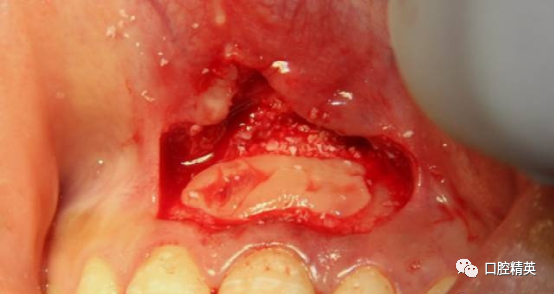

种植手机球钻轻打磨骨窝洞,直至暴露新鲜骨面。21根切倒充,玻璃离子充填。骨窝洞开血井,保证血供。

BIO-OSS骨粉混合PRF填补骨缺损。